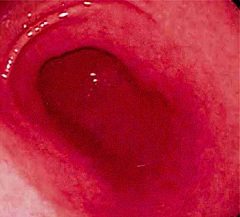

Для диагностики гастрита могут использоваться различные методы, включая гастроскопию, анализы крови, тесты на наличие Helicobacter pylori, а также рентгенографию с контрастом. Гастроскопия является наиболее информативным методом, позволяющим визуально оценить состояние слизистой оболочки желудка.